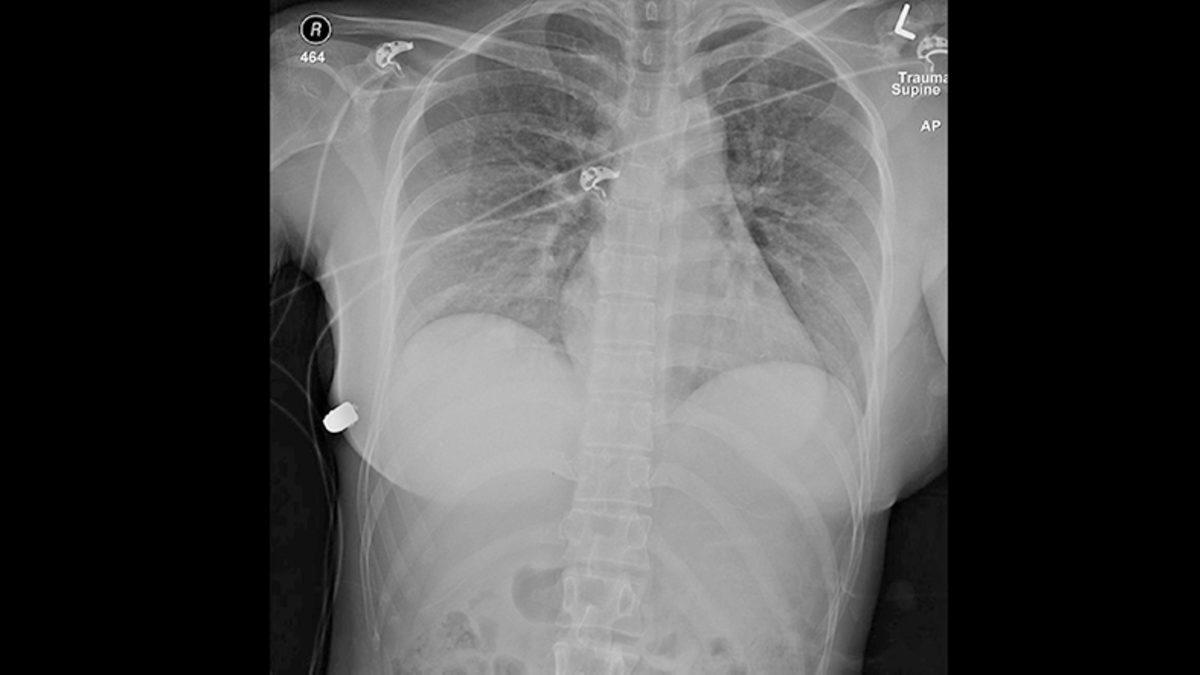

Acil serviste kadının sol göğüs ucunda belirgin bir ateşli silah yarası olduğu görülüyor. Silahla yaralanan kadın, müdahale için acil servisten bir travma merkezine sevk ediliyor ve burada katına müdahale ediliyor.

Müdahale edilen kadının, sol göğsünden giren merminin sağ göğüs duvarına kadar ulaştığı belirlendi. Doktorlar müdahale için ilk olarak kadının iki göğsünde bulunan silikonları çıkardı. Çıkarılan silikonlar doktorlar tarafından incelendiğinde, merminin sol göğüste bulunan silikonu delerek geçtiği görüldü. Doktorlar, sol göğüs silikonuna giren kurşunun saparak sağ göğüs silikonuna doğru gittiğini tespit ettiler.

Doktorlar, kadının sol göğsünde bulunan silikonun kalbinin hemen üstünde ve derin göğüs boşluğunda olduğu için kadının hayatını kurtarmasının muhtemel olduğunu söylüyorlar. Kurşunla yaralanan kadının sağ kaburgasında bir kemik kırıldı ve iki göğsünde bulunan silikon da çıkarıldı. Silikonların çıkarılmasının ardından doktorlar, kadının yarasını temizlediler ve önlem olarak kadına antibiyotik verdiler. Makalenin başyazarı plastik cerrah Giancarlo McEvenue, müdahalenin ardından kadının iyileştiğini bildirdi.